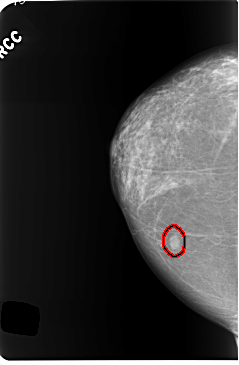

C_0255_1.LEFT_CC

LEFT_CC LINES 5912 PIXELS_PER_LINE 3560 BITS_PER_PIXEL 12 RESOLUTION 50 NON_OVERLAY

FILE: C_0255_1.RIGHT_CC.OVERLAY

TOTAL_ABNORMALITIES 1

ABNORMALITY 1

LESION_TYPE MASS SHAPE OVAL MARGINS CIRCUMSCRIBED

ASSESSMENT 4

SUBTLETY 5

PATHOLOGY BENIGN

TOTAL_OUTLINES 1

BOUNDARY